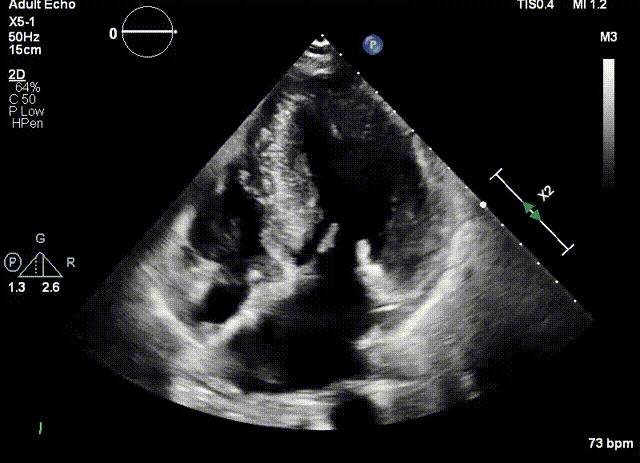

三位患者均患肥厚型梗阻性心肌病多年,因药物治疗效果不佳而到浙江大学医学院附属第二医院就诊。超声提示三位患者的室间隔呈非对称增厚,造成左室流出道梗阻。经团队评估决定进行超声引导下Liwen术式对室间隔进行消融。

患者是一位70岁的女性, 超声提示,患者室间隔最大厚度为20.8mm,静息状态下左室流出道重度梗阻,压差为118mmHg。负荷状态下122mmHg。